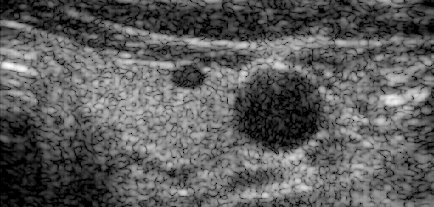

Alpinion_L3-8_FI_hypoechoic.uff

examples: advanced_beamforming